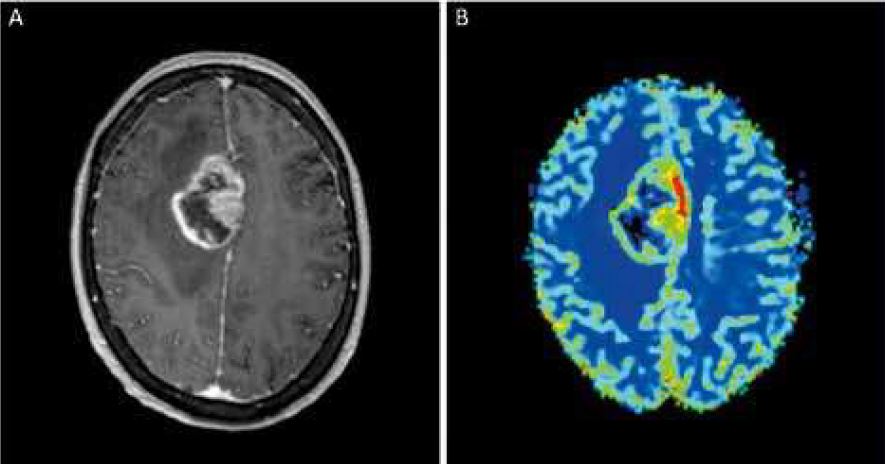

Soucieux d’offrir une meilleure résolution d’images, le service d’imagerie médicale vient d’équiper ses 2 IRM Siemens...